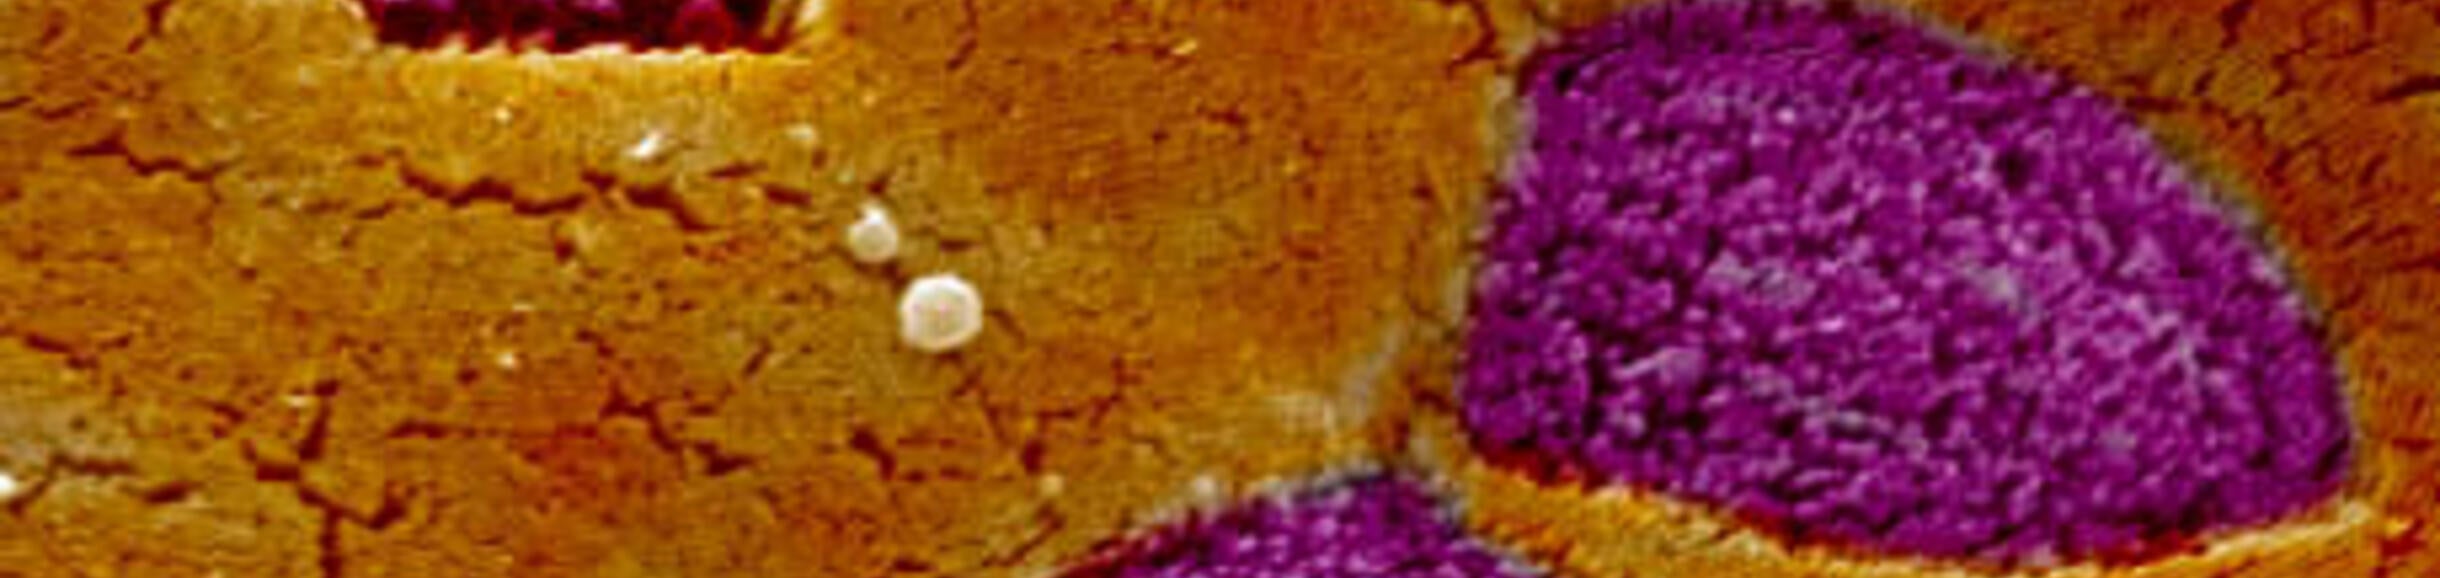

At mucosal surfaces, epithelial cells provide a tight barrier to entry into the body, but the immune system also induces the development of specialized epithelial cells called M cells to detect the presence of infectious organisms. These M cells are selective gatekeepers that capture particles such as viruses and bacteria for delivery to cells of the immune system waiting below the epithelial layer. Our laboratory has been studying the development of M cells, and the mechanisms used by M cells in their selective uptake of particles. We are also using the information we have learned about M cell function to engineer novel technologies for needle-free vaccine delivery that we hope to use against influenza and other infectious organisms. Several related projects are ongoing in our lab:

We have been using confocal microscopy approaches to identifying the cellular machinery used in the endocytosis and transport of bacterial particles by intestinal epithelial cells and M cells. Interestingly, M cells may use multiple mechanisms for transporting particles across the epithelial barrier. Our studies have already identified an unusual involvement of tight junction proteins such as Claudin 4 in one important pathway of bacterial particle uptake. We also showed that M cells produce cytoplasmic microvesicles that are delivered to underlying dendritic cells, providing a novel route for delivery of intracellular antigens.